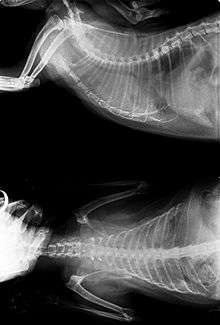

Cancer can be detected early on by observing for certain signs and symptoms. Common diagnosing methods include physical examination, x-rays, ultrasounds, cytology, blood tests, urine tests, and nuclear scans. Depending on the type of cancer and its level of progress, surgery, radiation, chemotherapy, or immunotherapy may be utilized to treat for cancer. Although research has been slow for causes and treatment of feline cancers, there have been advancements in radiation therapy, as well as newer and improved chemotherapy procedures.[2]

- X-rays (radiography) are divided by two types: plain film and constrat techniques. They are commonly used to present tumors of the lung, gastrointestinal tract, bladder, and other internal organs.